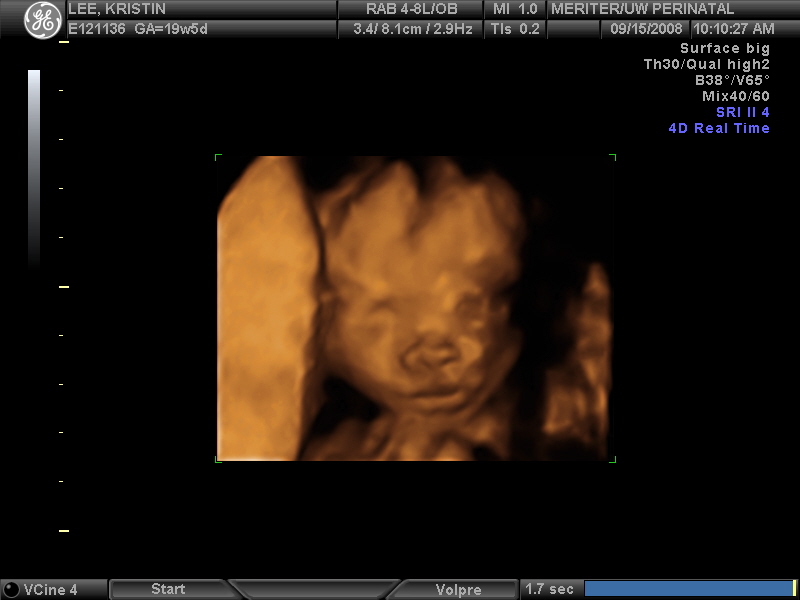

Ultrasound